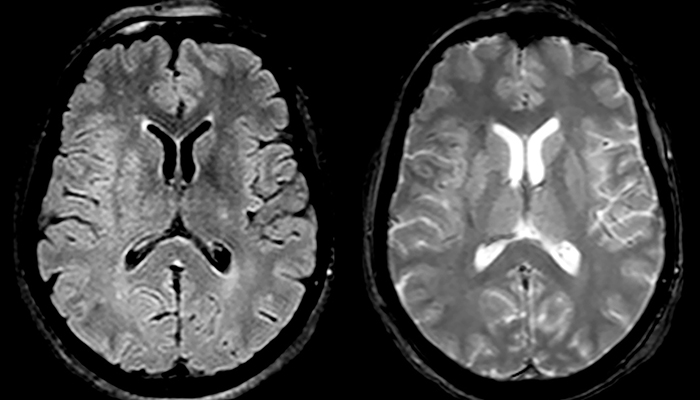

“In France, stroke is usually imaged with MRI, not CT, even for emergency treatment. This is because MRI helps us directly visualize ischemia in the acute phase, but can also help rule out differentials such as MS and hematoma. In addition, we can assess the intracranial and extracranial vessels during the same examination,” says Dr. Savatovsky.

The first challenge in MRI of stroke is speed. The patient typically arrives from an ambulance in the MRI preparation room and the installation is done on a separate dock outside the scanner room. “The venous access is placed during the neurological examination. If the delay from the first symptoms allows the patient to receive thrombolysis we do a very fast examination that typically lasts about 11 minutes including the pre-scans. In the case of transient ischemic stroke we usually add ASL perfusion because in some symptoms with negative diffusion, ASL sometimes indicates a vascular origin.”

“Ingenia provides great flexibility in the parameters setting. We can tune a sequence the way we want,” says Dr. Savatovsky. “For example, in a stroke exam we use a FLAIR sequence of about two minutes instead of the four-minute FLAIR we use for MS. The diffusion is 30 seconds, the T2*-weighted scan is 30 seconds, the angiography scan time is less than one minute. Ingenia is a great scanner in that situation; even with these fast sequences we can achieve good images with good SNR. When the first sequence tells us that it’s not an ischemic stroke but a hemorrhagic stroke, we may switch to a time-resolved angiography to look for vascular malformations and venous thrombosis.

“Every center is different, but for me the ideal protocol for stroke includes diffusion weighted imaging, FLAIR, and fast susceptibility imaging,” says Dr. Savatovsky. “Our fast susceptibility weighted imaging takes 50 seconds, so it’s as fast as T2*-weighted imaging. It visualizes hemorrhage but also the clots. We also do 3D MR angiography that provides information on cervical and brain vessels. If the patient does not need immediate treatment, or if additional information is needed to decide on treatment, we might also add perfusion imaging and post-contrast T1-weighted imaging.”